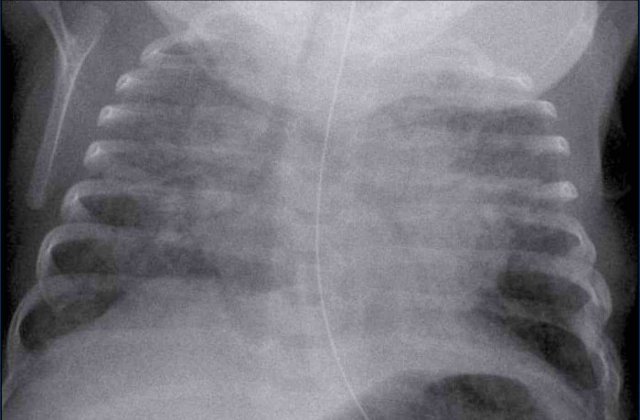

One day old neonate, 29 weeks of gestational age.

Image

• Hyperinflation due to CPAP.

• Granular opacification of both lungs with air bronchograms.

• NG tube in good position.

• Vessels and cardiac silhouette are harder to distinguish.

Conclusion: RDS grade 2.